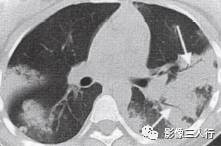

非典型肺炎的CT征象特点:分布不均匀、形态不同、大小不一的肺实变是本组 患者共同存在的基本CT表现。肺实变通常由于肺泡内充盈浆液性、渗出性或血性液 体、炎细胞或其他成分,导致肺实质弥漫性或局灶性密度增高。早期表现为边界不 清楚的0.5〜1.0cm的结节性高密度灶,随着病变的进展,融合成团块或斑片状阴 影,掩盖肺血管纹理。较大的实变影像内可见支气管分支的透亮影则为空气支气管征。见图9。